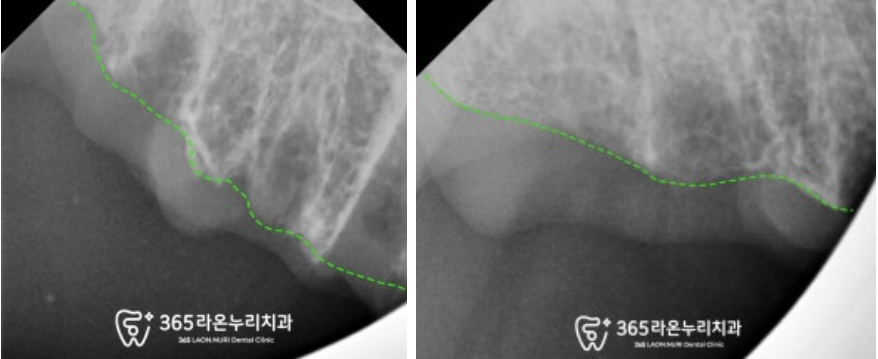

아 물론 뿌리를 단단하게 잡아주고 있는

치아도 몇개 있습니다.

그래서 조금이라도 본인의 이를 더 사용하실 수 있도록

몇개의 이는 크라운을 진행해

틀니를 더욱 단단하게 고정하는 용도로

활용하기로 했습니다.

상악은 틀니를 하게 될 경우

입천장과 닫는 면적이 넓어

상대적으로 유지력을 얻기 좋을 거 같아

이와 관련된 내용을 설명드렸으며